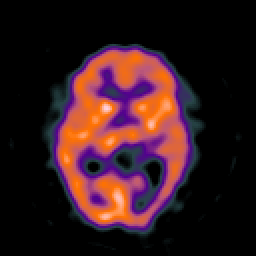

SPECT TC Study #8 -- Slice #27

[Home][Help][Clinical][Tour 1][Tour 2][Tour 3] Slice 27